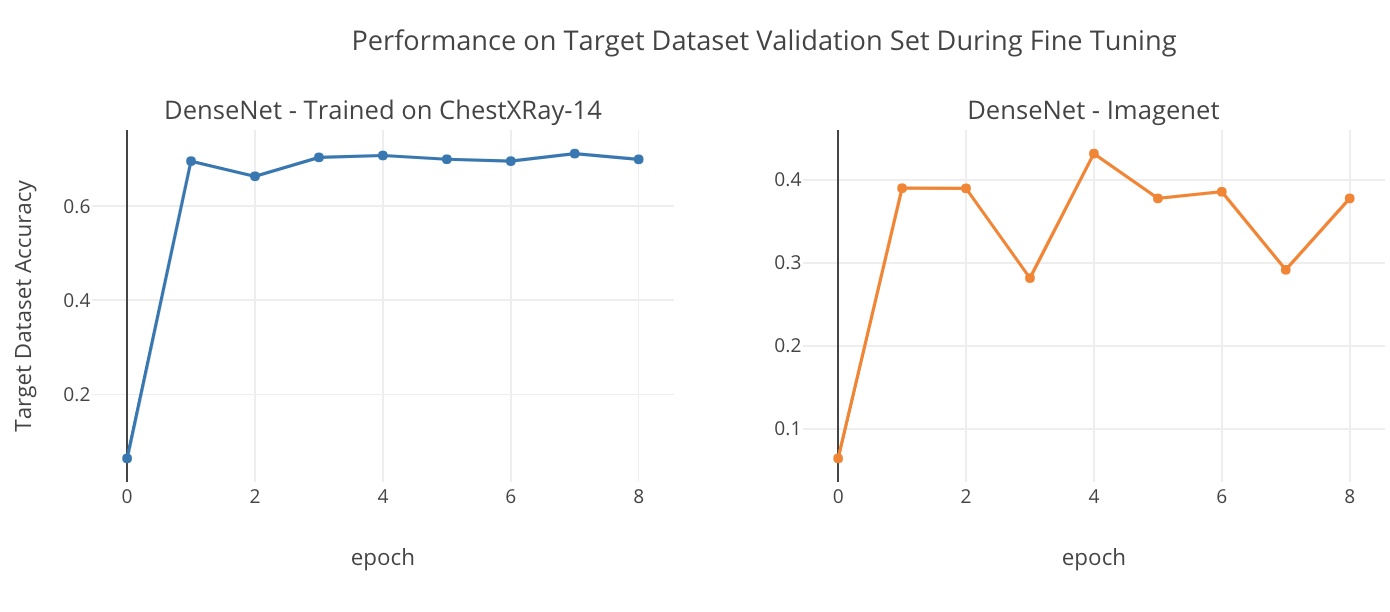

Transfer learning is the crux of the image model. As we have done previously with the embedding layer in the text model, this work checks for generic feature performance in the image model as well. The generic feature’s performance is assessed by transferring encoders trained on ImageNet and domain specific features are assessed with encoders trained on Chestxray-14. Densenet121 (Huang, 2017) is chosen to be used as the encoder due to dense connections. Figure 4 shows the performance of these two different transfer learned models on the Indiana University dataset’s validation set during fine tuning.